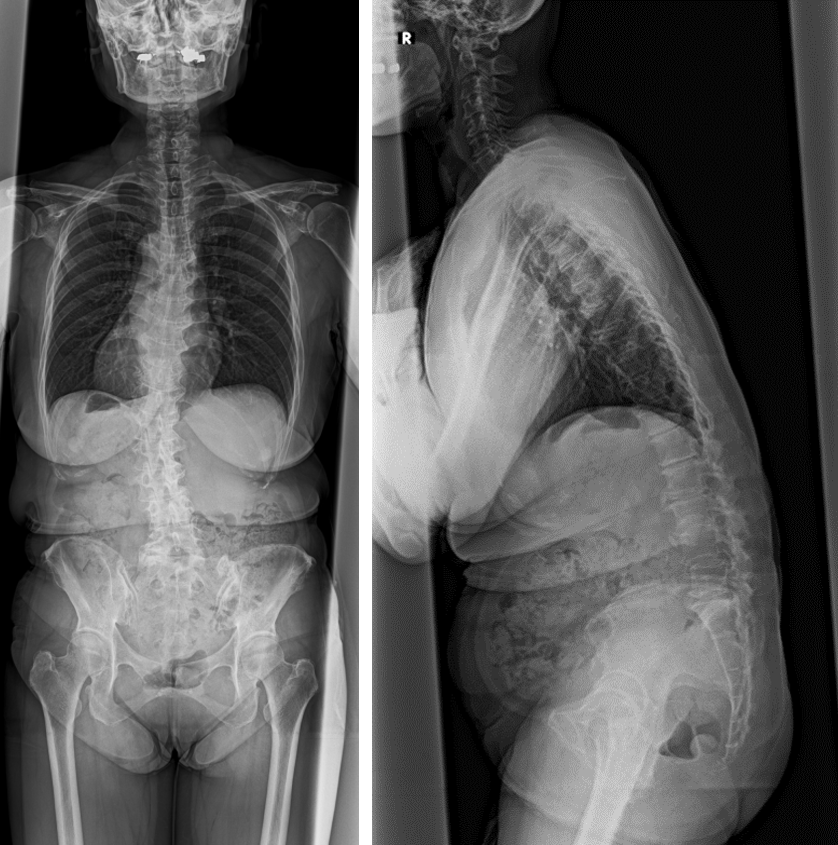

成人脊柱変形 変性後弯症・側弯症- 東京科学大学 整形外科。